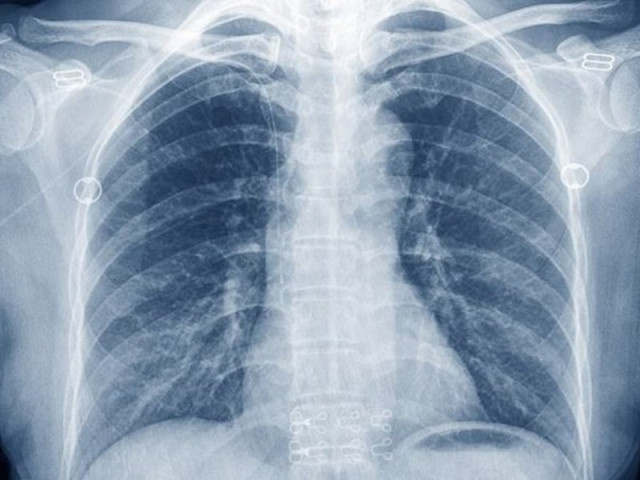

Med: умирающий пациент двое суток провел без легких и пошел на поправку

фото: Медикфорум